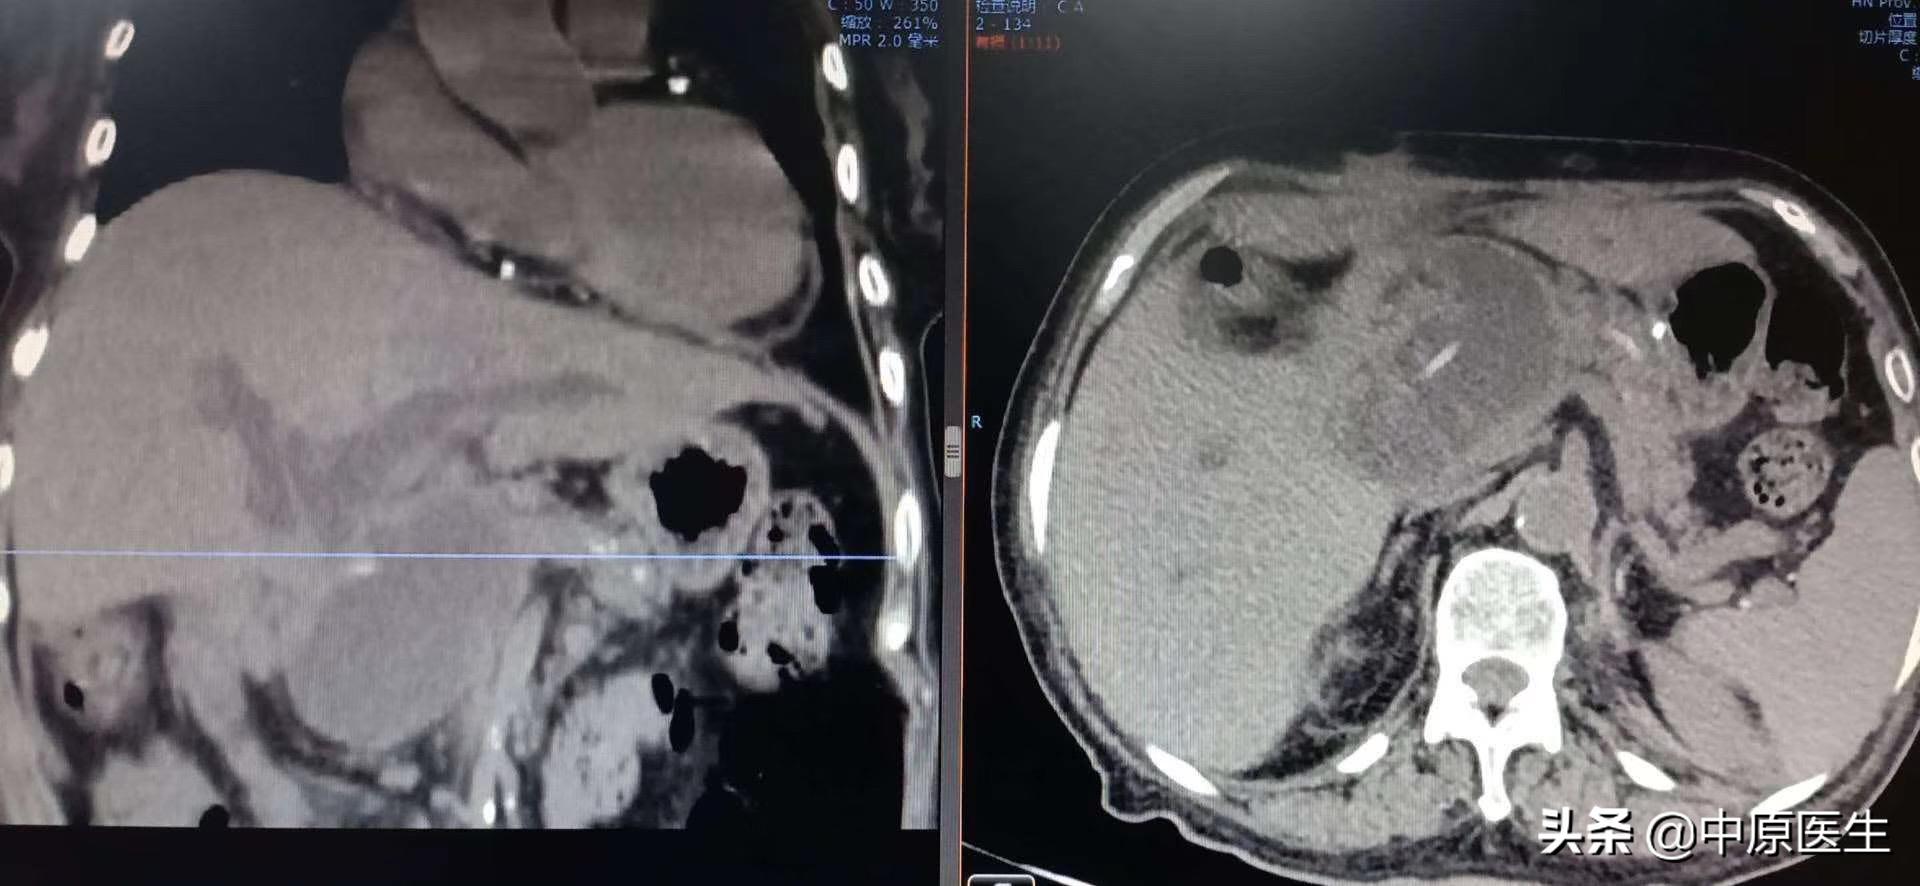

这是一个胰十二指肠切除术后的老太太、曾经做过胆肠吻合,肠管狭窄导致严重胆管梗阻和感染的病人,虽然经过内科规范治疗,仍然反复高热,感染无法控制。

经过消化内科多位专家,肝胆外科专家还有我们介入科专家共同会诊,建议找我做经皮穿刺胆管引流术(PTCD)、肠管狭窄球囊扩张术。

经过我认真查阅检验结果和影像资料,发现血培养结果:屎肠球菌、阴沟杆菌双细菌感染,多种抗生素耐药;有电解质紊乱。查看患者,体质极度衰弱,这就是合并了梗阻性化脓性胆管炎,一个要命的急症!通过十二指肠镜做ERCP?镜子过不去!再做外科手术?无论是患者的状态,还是局部解剖结构的紊乱,都很难实施!我与家属反复交代了介入治疗手术操作的方法、风险等,并且签署了手术协议书。

经过消化内科积极准备,病人当天晚上就躺了我们的术台上,那时的患者,正在寒颤,我们迅速消毒,铺巾,准备好手术器械,定位、局麻,从右侧胸壁腋中线第十肋间一针穿刺进入肝右胆管,依次送入扩张鞘,导丝,外引流管,随即就抽出了瘀滞的带味道(感染细菌发出来的味道)的墨绿色、带沉渣的胆汁和肠液约100多毫升。因为患者寒颤,身体情况太差,所以我们放弃了再仔细寻找狭窄肠管部位的手术(这时候保命要紧,那个手术可以择期再次进行),冲洗引流管后,固定、包扎。把患者安全转入介入科病房。回到病房十多分钟后,患者的腹胀、寒颤都有了明显减轻。精神状态也好了很多。看着自家老人转危为安,这一家子说了数不清感激的话!

我们做这个经皮穿刺胆管造影+引流管置入术(PTCD)是怎么一回事呢?它是在影像设备引导下,用一根21G(0.80mm)的细穿刺针经皮经肝穿刺胆管,并置入引流管,使胆汁流向体外或十二指肠的一系列技术。主要用于胆道梗阻和急性炎症的治疗。PTCD不受胆管手术影响(如胆肠吻合术等),对患者的身体要求相对较低,创伤小,缺点是对原发病的治疗有时候会力不从心。